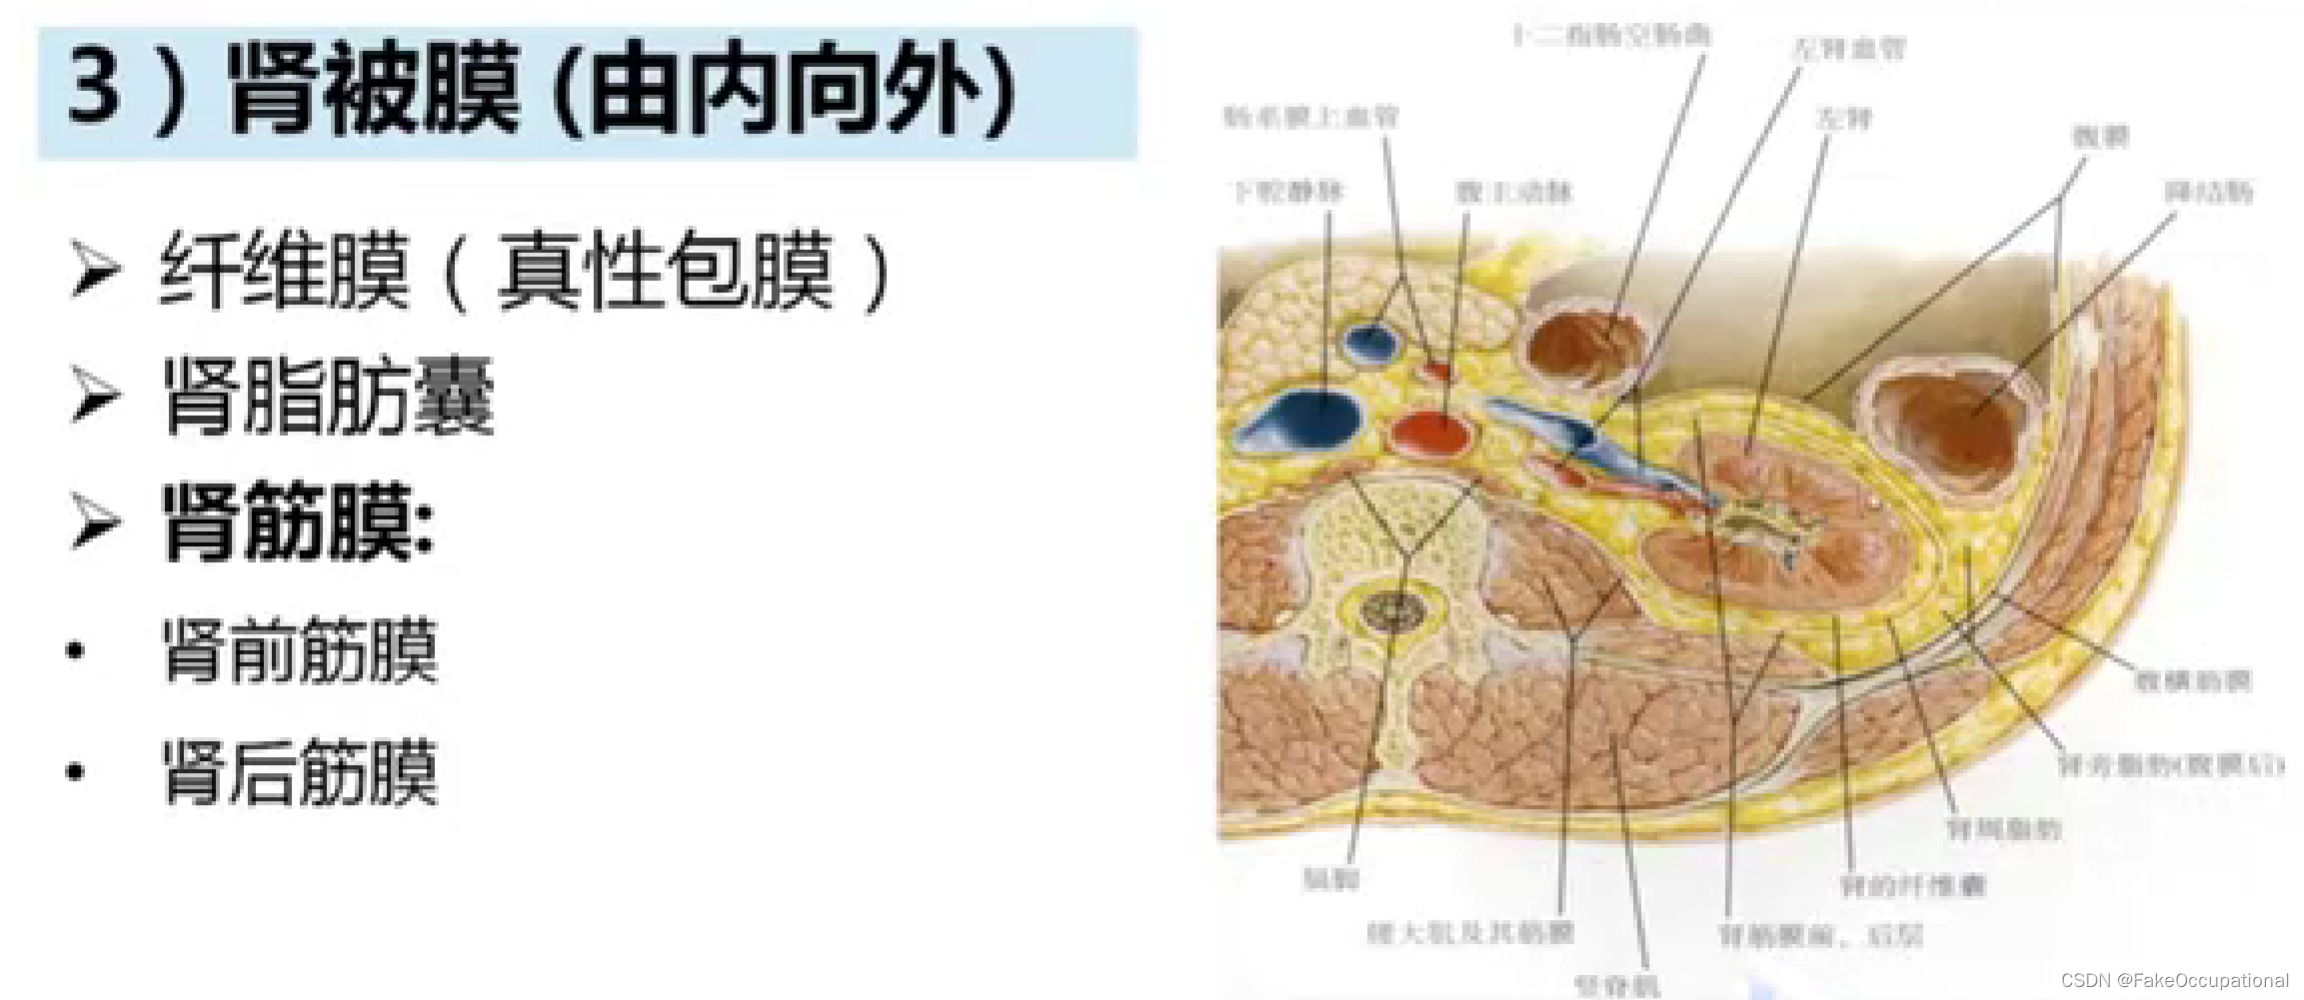

肾脏解剖概要